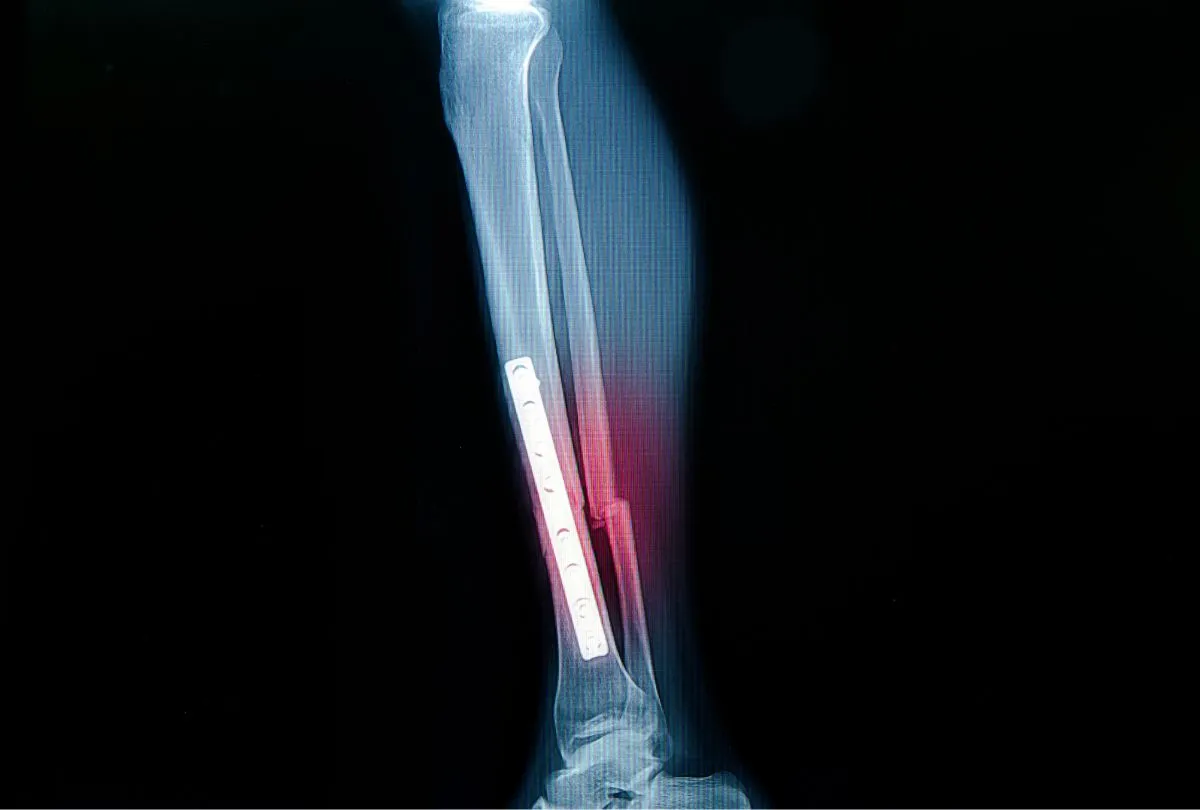

Gdy zgłosisz się do lekarza z podejrzeniem złamania kości strzałkowej, pierwszym i najważniejszym badaniem, które potwierdzi diagnozę, jest zdjęcie rentgenowskie (RTG). To tzw. złoty standard w diagnostyce urazów kostnych. Pozwala ono na precyzyjne uwidocznienie linii złamania, ocenę jego charakteru, lokalizacji oraz ewentualnego przemieszczenia odłamów kostnych.

Na czym polega zespolenie kości płytkami i śrubami? W trakcie zabiegu chirurgicznego, ortopeda używa specjalnych implantów, takich jak płytki, śruby lub gwoździe, aby połączyć ze sobą odłamy kostne. Pozwala to na uzyskanie stabilnego zespolenia, które umożliwia wczesne rozpoczęcie rehabilitacji i znacząco zwiększa szanse na prawidłowe zrośnięcie się kości. Szczególne znaczenie ma tu precyzja wykonania, zwłaszcza gdy złamanie dotyczy okolicy stawu skokowego, gdzie dokładne odtworzenie anatomii jest kluczowe dla jego prawidłowego funkcjonowania.